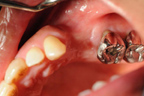

左上顎第一、第二小臼齒缺損。

施行鼻竇升高術及骨粉充填。